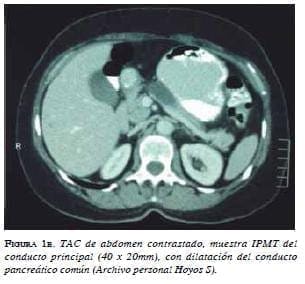

Dada la asociación que existe entre el tumor papilar intraductal mucinoso con el cáncer extrapancreático (gástrico y colorrectal, principalmente) 15, es importante descartar cualquiera de estas dos neoplasias una vez se haya hecho el diagnóstico del quiste pancreático, ya que hay series que reportan tasas de correlación que van desde 8,5 hasta 16,8 % para los occidentales 16 y de 30 a 38 % para los orientales 17. La diferencia entre los orientales y los occidentales podría ser difícil de explicar, pero puede deberse a las diferencias regionales en la incidencia individual del cáncer 18 (figuras 1a y 1b)

![]() |